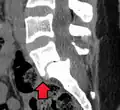

Degenerative spondylolisthesis at L5-S1.

(A) CT sagittal view of a low grade slip.

(B) Lateral radiograph pre-operative intervention.

(C) Surgically treated with L5–S1 decompression, instrumented fusion and placement of an interbody graft between L5 and S1.